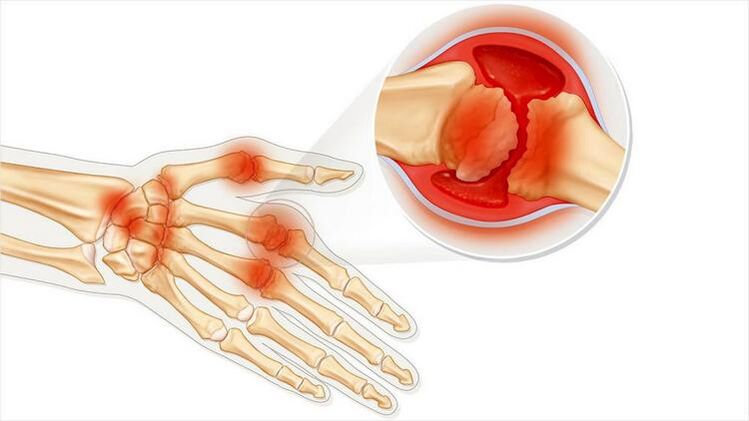

Kloubní artritida je stav zánětu kloubů. Hlavně vyjádřeno jako otok a zarudnutí. Vnitřní výstelka kloubu je zničena, což vede k bolesti, kterou je často obtížné jednoduše vydržet.

Artritida je charakterizována následujícími rysy:

- Pokud se kůže poblíž kloubu zčervená, může nastat horečka.

- Změna vzhledu kloubu.

- Nádor.

- Bolestivé pocity při pohybu.

- Při stisknutí kloubu nepříjemné pocity.

- Artritida může být infekční onemocnění. Pak se objeví všechny příznaky odpovídající infekcím: zlomený stav, horečka, zimnice.

Artritida může ovlivnit jeden kloub nebo několik. Vyskytuje se s akutní bolestí nebo postupně a způsobuje chronické onemocnění. Pak dojde k tupé bolestivé bolesti.